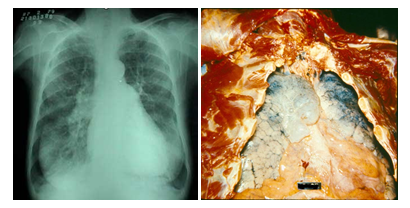

EPOC: Enfermedad en estudio

El EPOC, es la etapa Previa de Cancer Púlmonar, “Espirometría”